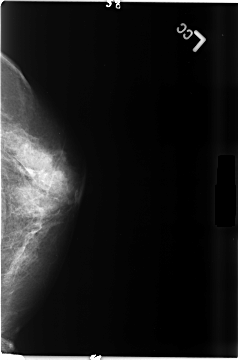

B_3480_1.LEFT_MLO

LEFT_CC LINES 4672 PIXELS_PER_LINE 3088 BITS_PER_PIXEL 12 RESOLUTION 50 NON_OVERLAY